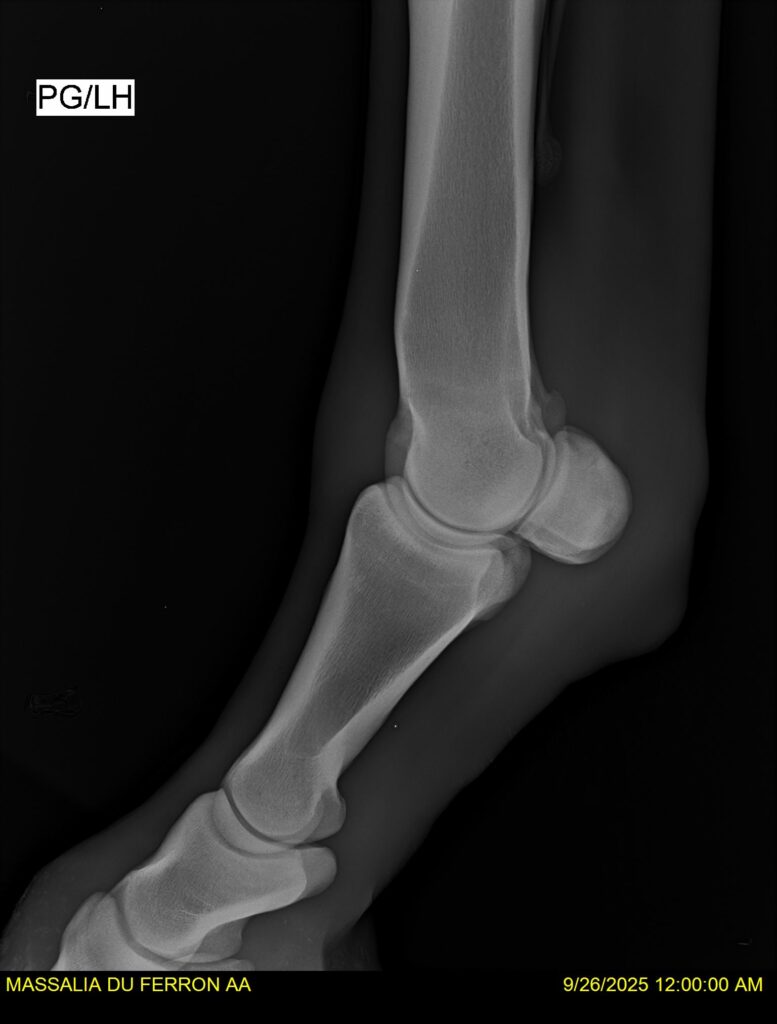

MASSALIA DU FERRON, jument qui prendra 4 ans par PRESTIGE KALONE x TRESOR DU RENOM. Un mental en or et un véritable sens de la barre ! Facile d’accès ! Bonne énergie et bons moyens. Souche moderne et très intéressante. Transport OK, maréchalerie OK, santé RAS, Bilan clichés radios OK.

RADIOS et COMPTE RENDU